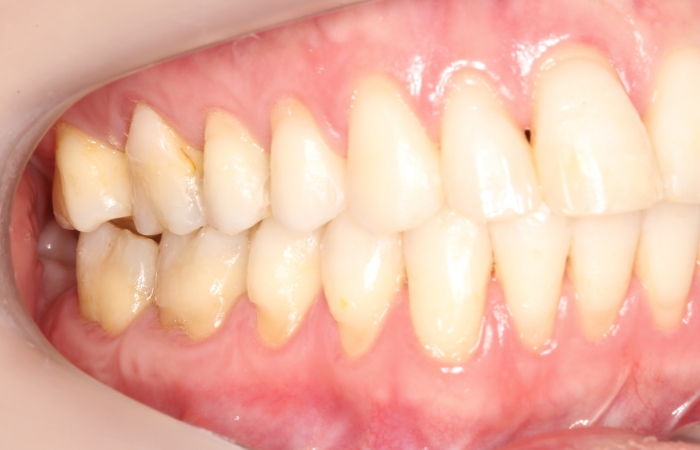

Oclusão após a cirurgia